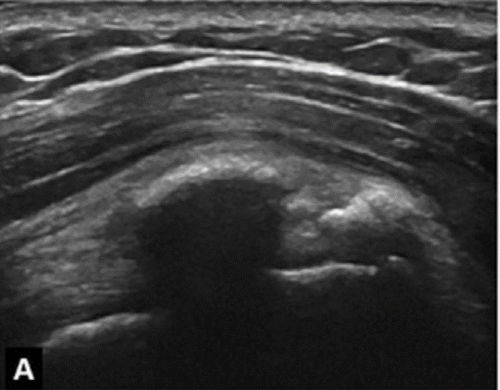

Υπερηχογραφική απεικόνιση της ασβεστοποίησης του ώμου (Farin)

Στην κλινική πράξη είναι αυτή που δίνει τις πιο αξιόπιστες πληροφορίες για τη σύσταση της ασβέστωσης.

| Τύπου Α: Υπερηχογενής με έντονη ακουστική σκιά | Τύπου Β: Υπερηχογενής με ήπια ακουστική σκιά | Τύπου C: Υπερηχογενής χωρίς ακουστική σκιά |

Με βάση αυτή την ταξινόμηση μπορούμε να εκτιμήσουμε την αποτελεσματικότητα μιας θεραπείας Barbotage

Με λίγα λόγια, όταν η ασβέστωση είναι μαλακής ή μέτριας σκληρότητας, το αποτέλεσμα της θεραπείας Barbotage προβλέπεται άριστο/πολύ καλό ενώ αν είναι σκληρής σύστασης τότε το αποτέλεσμα θα είναι μέτριο/φτωχό

(καλύτερη ένδειξη για barbotage: ασβέστωση Farin B και C , Gartner/Hayer II,III)